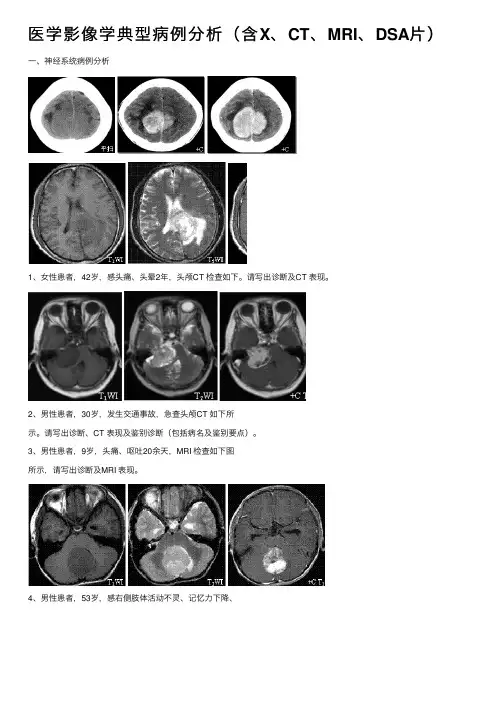

医学影像学典型病例分析(含X、CT、MRI、DSA⽚)⼀、神经系统病例分析1、⼥性患者,42岁,感头痛、头晕2年,头颅CT 检查如下。

请写出诊断及CT 表现。

2、男性患者,30岁,发⽣交通事故,急查头颅CT 如下所⽰。

请写出诊断、CT 表现及鉴别诊断(包括病名及鉴别要点)。

3、男性患者,9岁,头痛、呕吐20余天,MRI 检查如下图所⽰,请写出诊断及MRI 表现。

4、男性患者,53岁,感右侧肢体活动不灵、记忆⼒下降、失写半个⽉,MRI 检查如下,请写出诊断、MRI 表现及鉴别诊断(包括病名及鉴别要点)。